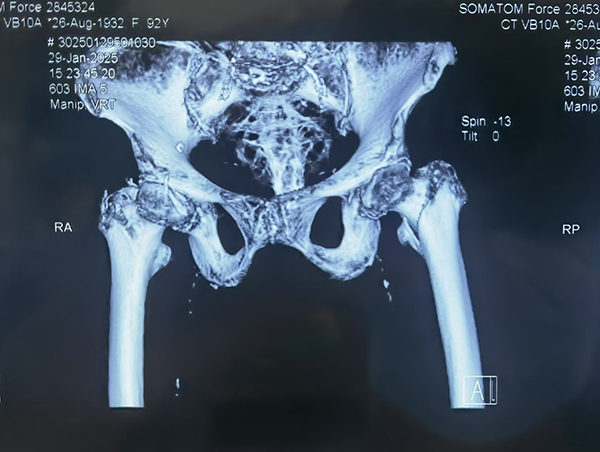

除夕夜,92岁的李奶奶不慎摔倒,导致股骨粗隆间骨折。这一常见于老年人的髋部骨折,因其高发病率和严重的并发症风险,一直是老年健康的重大威胁。受伤后,李奶奶被紧急送往省立医院中心院区。省立医院创伤中心是山东省创伤中心、山东省创伤质控中心挂靠单位,国家创伤区域医疗中心建设单位,在老年髋部骨折的手术治疗方面积累了丰富的经验。面对高龄患者常伴有的多种基础疾病,以及手术风险极高的挑战,创伤中心医疗团队迅速启动紧急救治流程。

创伤中心主任医师王伯珉、王大伟医疗团队对李奶奶的身体状况进行了全面而细致地评估,制定了详细且个性化的手术方案,并同患者家属进行了充分的沟通。考虑到高龄患者的身体耐受性,手术团队精心选择了微创手术方式,以期最大限度减少手术创伤和术后并发症的发生。在麻醉手术科团队的紧密配合下,手术过程顺利,李奶奶的骨折得到了精准修复。